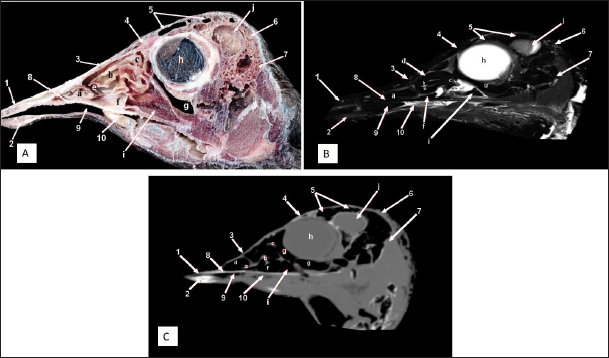

Fig. 9. Rostral-caudal cross sections of the adult ostrich head—level 4. Rostral views of A) photograph of an anatomical cross section, B) MRI and C) computed tomography images showing: 1- Os frontalis, 2- Frontal sinus, 3- Processus quadratojugale, 4- Eye ball, 5- Pars verticalis ethmoidale, 6- Infra orbital sinus, 7- Vomer, 8- Tracheal lumen surrounded by tracheal cartilaginous rings, 9- Sagittal eminence (wulst) of the cerebrum. Caudal views of D) an anatomical cross section, E) MRI and F) computed tomography images showing: 1- Os frontalis, 2- Processus. quadratojugale, 3- Vomer, 4- Eye ball, 5- Infra orbital sinus, 6- Trachea, 7- Cerebral hemispheres of the brain.

Fig. 10. Rostral-caudal cross sections of the adult ostrich head—level 5. Rostral view of A) photograph of an anatomical cross section, B) MRI and C) computed tomography images showing: 1- Os parietale, 2- Os basisphenoidale, 3- Cerebral hemispheres, 4- Mid brain, 5- Trachea Plate. Caudal views of D) an anatomical section, E) MRI and F) computed tomography images showing: 1- Os parietale, 2- Os basioccipitale, 3- Cerebellum, 4- Pons, 5- Trachea, 6- Os temporalis.

Cranium and brain

The ostrich’s cranial cavity was bounded by frontal bone dorsally, basioccipital and basisphenoid bones ventrally, supraoccipital and parietal bones caudally, interorbital septum rostrally, and temporal bone laterally. The parietal, sphenoid, and temporal bones were pneumatic (Figs. 2, 3, 9, and 10).

The brain was divided into three parts: the hindbrain (medulla oblongata and cerebellum), the midbrain (cerebrum’s peduncles and optic lobes), and the forebrain (thalamus, pineal body, hypophysis, optic tracts, and chiasm, cerebral hemispheres, and olfactory lobes) (Figs. 2, 9, and 10). The sagittal section of the brain includes the olfactory bulb, cerebrum, cerebellum, medulla oblongata, optic lobe, optic chiasm, and hypophysis (Fig. 2). The dorsal median longitudinal fissure separates the cerebrum into two hemispheres. The sagittal prominence (west) was present on both sides of this fissure (Figs. 9 and 10).

The CT pictures revealed the skull as a readily discernible white structure due to its high CT density, while the brain appeared as a grey structure due to its intermediate density. However, the settings utilized made it impossible to identify different areas of the brain in the CT scans (Figs. 9 and 10C, F). The MRI pictures showed the brain as a whitish structure with a high signal intensity. This technique was used to identify various brain structures, including the hindbrain (medulla oblongata, and cerebellum), the midbrain (peduncles of the cerebrum, optic lobes), and the forebrain (thalamus, pineal body, hypophysis, optic tracts and chiasm, cerebral hemispheres, and olfactory lobes) (Figs. 2B, 9 E, and 10E). Additionally, the olfactory bulb, cerebrum, cerebellum, medulla oblongata, optic lobe, optic chiasm, thalamus, and hypophysis.